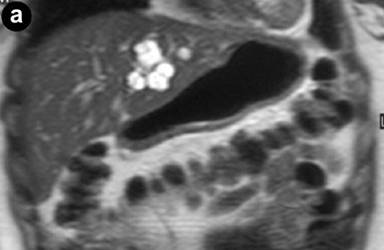

A 27-year-old female underwent a cholecystectomy for lithiasis. The patient was successively evaluated for diffuse and recurrent abdominal pain; no alcohol and/or smoking habits were reported. Laboratory measurements of total bilirubin and pancreatic amylases were unremarkable. Abdominal ultrasound was carried out which showed multiple hepatic and pancreatic cystic lesions; a dynamic enhanced CT scan confirmed the presence of multiple liver and pancreatic cystic lesions, but, in particular, the differentiation between simple hepatic cysts and cystic ectasia of the biliary ducts suggestive of Caroli’s disease was not reached. Therefore, MRI was requested to characterize the liver lesions and it was performed acquiring T1- and T2-weighted sequences integrated with T2-hydrographic images to specifically evaluate the biliary tract in axial and coronal views. MR cholangiography after intravenous administration of mangafodipir trisodium (Teslascan®, Nycomed, Amersham, Oslo, Norway), was also performed using T1-weighted sequences. Turbo spin echo T2-weighted images in axial and coronal views showed multiple hyperintense focal lesions in the left lobe of the liver, typical of cystic lesions, as well as multiple pancreatic cysts of the tail and saccular ectasia of the main biliary duct (Figure 1). T2-hydrographic dedicated images confirmed these findings, but certain imaging signs for a differential diagnosis between simple hepatic cysts and biliary cysts were not identified (Figure 2). However, the enhanced mangafodipir trisodium T1-weighted MRI clearly showed that some of the liver cysts concentrated mangafodipir trisodium contrast medium, thus demonstrating that these enhanced cystic lesions were in communication with the biliary ducts providing imaging criteria consistent with a diagnosis of Caroli’s disease (Figure 3). A segmental hepatectomy specimen demonstrated dilated simil-cystic intrahepatic ducts of the IV segment corresponding to a diagnosis of Caroli’s disease.

Figure 1. Conventional turbo spin echo T2-weighted axial (a., b. and c.) and coronal (d.) MR views show multiple cystic lesions in the left liver lobe as well as in the pancreatic tail. Saccular ectasia of the main biliary duct is also depicted. |